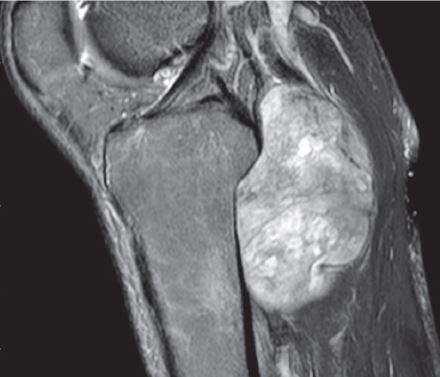

It is a procedure that involves removing a tumor (usually malignant or benign aggressive) of the posterior knee compartment (back of knee) while preserving the surrounding bone and soft tissues.